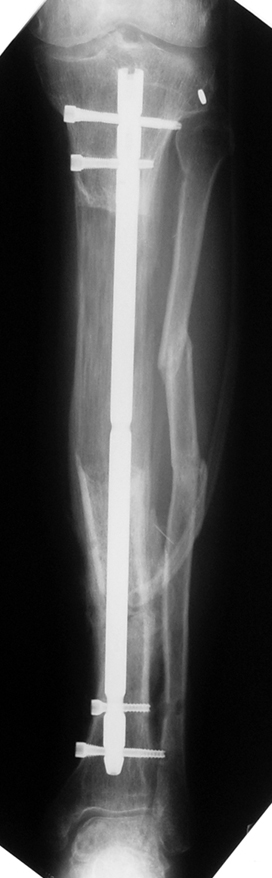

Appropriate radical debridement necessitates excision of all necrotic bone and soft tissues, and frequently causes instability at the involved extremity. The remaining bone and soft tissue defect has to be fixed and reconstructed. The distraction osteogenesis method of Ilizarov is used successfully for achievement of union, correction of the deformity, elimination of limb length inequality and reconstruction of segmental bone defects.

The duration of external fixation (external fixation index) depends on the amount of distraction required, and the extremity is prone to complications during this period. After the distraction phase is completed, the external fixator remains in place during the consolidation phase, which lasts twice as long as the distraction phase; but this period is hardly tolerated. If the external fixator is removed before sufficient consolidation is achieved, fractures, deformity and shortness will be the result. In our department, ‘lenghthening over nail’ method is used in order to decrease the external fixation index and increase patient comfort and activity level. In this method, the intramedullary nail is statically locked after the completion of the distraction phase, and external fixator is removed. The extremity is stabilized by the intramedullary nail during consolidation phase. In this way, complications due to long external fixation index or early removal of the external fixator are avoided.